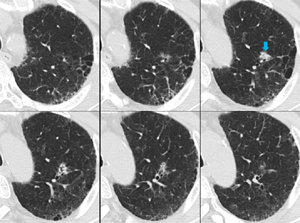

両肺に数少ないが多発結節(小葉との関係は判断困難)の出現、出現速度は速く、増大経過(LVFX抵抗性)

増大したものの一部に空洞形成、左上区の最大のものの空洞内には同心円状・索状構造がみられる

数日後という短時間で血液培養から抗酸菌が検出された→Rapidly growing mycobacterium (RGM)による敗血症と診断(図6)(図7)(図8)

抗菌薬(主にアミカシン)で加療され、肺病変は縮小